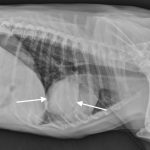

Understanding Lung Cancer in Dogs: Symptoms, Diagnosis, and Treatment

Discover essential insights on lung cancer in dogs, including symptoms, diagnosis, treatment options, and prevention strategies to ensure your pet’s health and well-being.